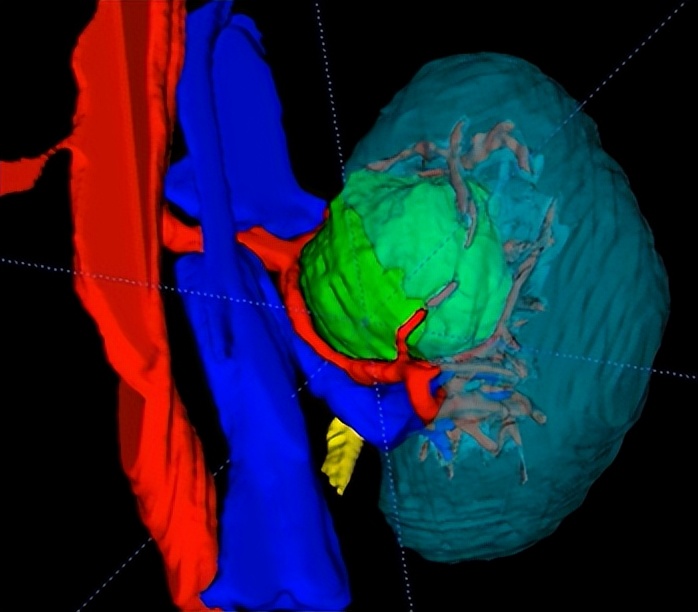

在手术前,朱绍兴教授团队利用3D成像技术,将CT影像二维数据在计算机上进行三维重建,将肾脏血管、集合系统与肿瘤的空间关系做了多角度的直观显示,进而制定了详实的手术计划和预案。

▲图1:术前肾脏CT影像及三维重建图,可见肿瘤嵌入肾门中央,被肾脏大血管所包绕(红色箭头所指处为肾肿瘤,三维重建图中绿色部分为肾肿瘤、红色部分肾动脉、蓝色部分为肾静脉、青色部分为肾脏、黄色为输尿管肾盂)

“以前就算开刀进入肾脏内部,也无法看得这么清楚。现在通过三维重建技术,医生在术前就能准确地评估病变周围情况,依此模拟手术场景、规划手术路径,为最大限度地在切除肿瘤的同时,保留肾内大血管和其他重要结构且最大程度地保留肾单位奠定基础。” 02 精确定位肿瘤:腔内超声“透视眼”助力精准定位肿瘤